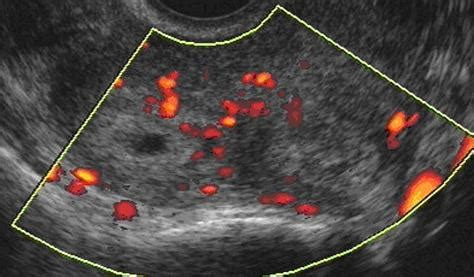

Pomembno je poudariti, da se prezgodnji porod včasih lahko začasno ustavi, vendar to ne pomeni, da zdravnik ne bo mogel ustaviti poroda. Ukrepi ob grozečem prezgodnjem porodu vključujejo hospitalizacijo, transport "in utero" (med nosečnostjo), ultrazvočno oceno materničnega vratu, velikosti ploda in količine plodovnice, določitev lege posteljice, vstave in lege ploda. Ob vaginalnem pregledu se odvzame bris nožnice na patogene bakterije, naročijo pa se tudi laboratorijski izvidi glede na klinično sliko.

- Težave z materničnim vratom: Šibkost materničnega vratu (insuficientno maternično ustje) pomeni, da maternično ustje ni dovolj močno, da bi zadržalo nosečnost do konca. Znaki, kot so bolečine v križu, bolečine v spodnjem delu trebuha, občutek tiščanja navzdol ali nenavaden izcedek, lahko nakazujejo na težave z materničnim vratom. Dolžina materničnega vratu, izmerjena z vaginalnim ultrazvokom, je ključen pokazatelj; krajši kot je vrat, večja je verjetnost za prezgodnji porod. Pri prvorodkah lahko maternični vrat, krajši od 15 mm med 20. in 24. tednom nosečnosti, pomeni veliko verjetnost za prezgodnji porod.